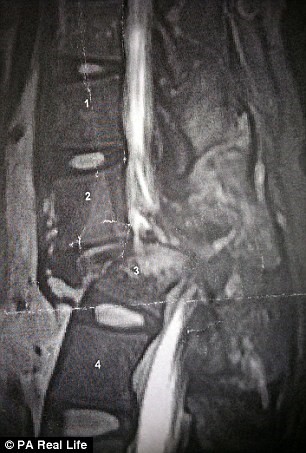

При ужасното падане девойката и счупила двете ключици, 6 ребра и гръбнака. Сблъсъкът с пътния знак й причинил множество травми на женските органи, а тялото й било парализирано от гърдите надолу. Мнозина на нейно място щяха да изпаднат в отчаяние, но Меган не се предала.

Нещастното момиче преживяло множество операции. Специалистите й закрепили гръбнака с метални скоби и успели да възстановят донякъде увредените й органи. Така Меган започнала отново да идва в спортната зала, но сега в инвалидна количка. Всеки ден тя полагала неимоверни усилия да започне да става отново и направила първата крачка.